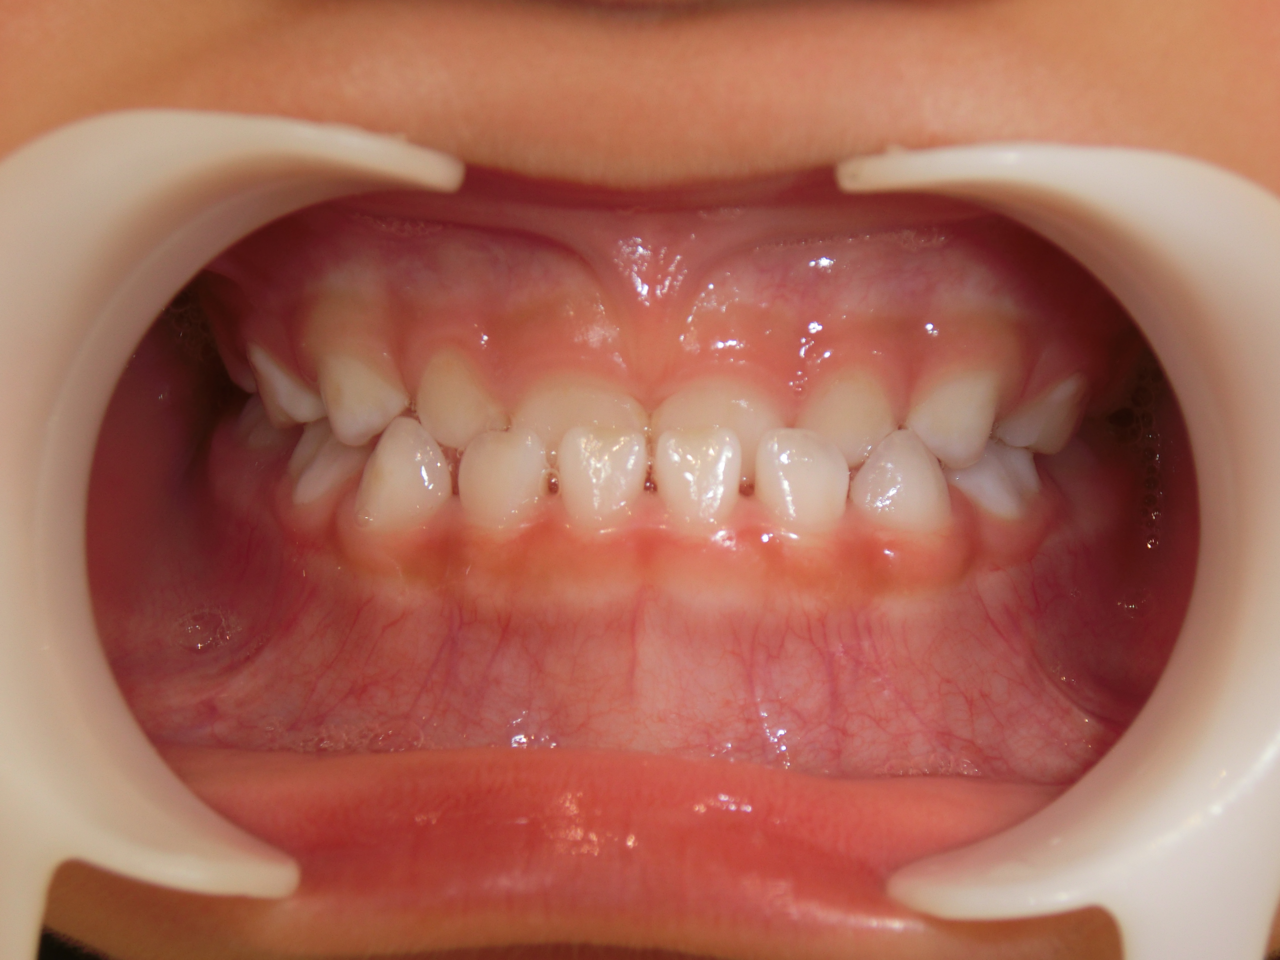

治療前

治療説明 歯科矯正で取り外し可能な矯正方法である床矯正で治療しました

治療期間 2年1か月

治療費200000 円

治療後

治療の副作用(リスク)歯の動き方には個人差があり、予想された治療期間が延長する可能性があります。。床矯正の使用状況、矯正歯科治療には患者さんの協力が必要であり、それらが治療結果や治療期間に影響します。2次矯正が必要になる場合もあります。